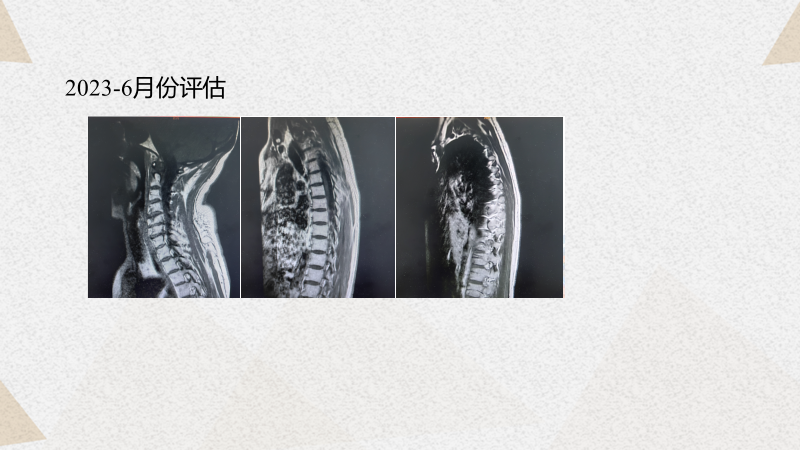

杨华教授:回顾整个病程,从21年6月患者确诊以来,两年的时间里经历了非常艰难的一系列治疗:21年7月份在TA新方案之后出现了脑转移,局部伽玛刀治疗后更换为TP+贝伐珠单抗。后续基因检测后,更换为TC+贝伐珠单抗,疗效不理想,则进一步使用了NX+卡瑞利珠单抗治疗了4个周期,但因副作用而停药。22年7月又出现了腋窝淋巴结的进展并且破溃,继而更换为艾立布林+帕博利珠单抗但效果不理想。从22年11月开始使用DS-8201(T-DXd,德曲妥珠单抗)至今。我们可以从患者有限的影像学的资料中看到一个相对理想的效果,可以说DS-8201(T-DXd,德曲妥珠单抗)给患者提供了新的疗效升级。